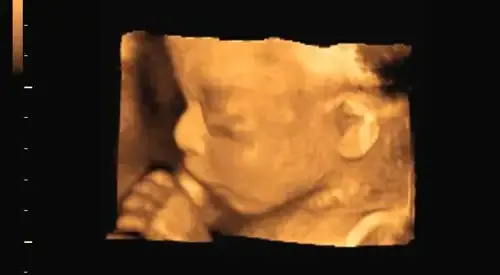

La ecografía 4D es la imagen en tres dimensiones (ancho, largo, profundidad y tiempo), obtenida por ultrasonidos y en un tiempo real, de un feto, es decir, permite observar el feto en movimiento real.

Además, las ecografías 4D resultan excelentes herramientas para estudiar la actividad motora y fisiológica del feto.

La ecografía es una de las técnicas más importantes en el diagnóstico prenatal y en los últimos años ha experimentado un extraordinario desarrollo.